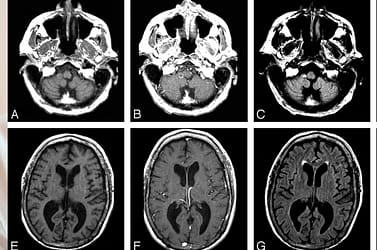

Se você ou um ente querido foi diagnosticado com melanoma cerebral em estágio 4, você …

Tratamento Natural de Melanoma Cerebral em Estágio 4 com Metástase Mais informação »